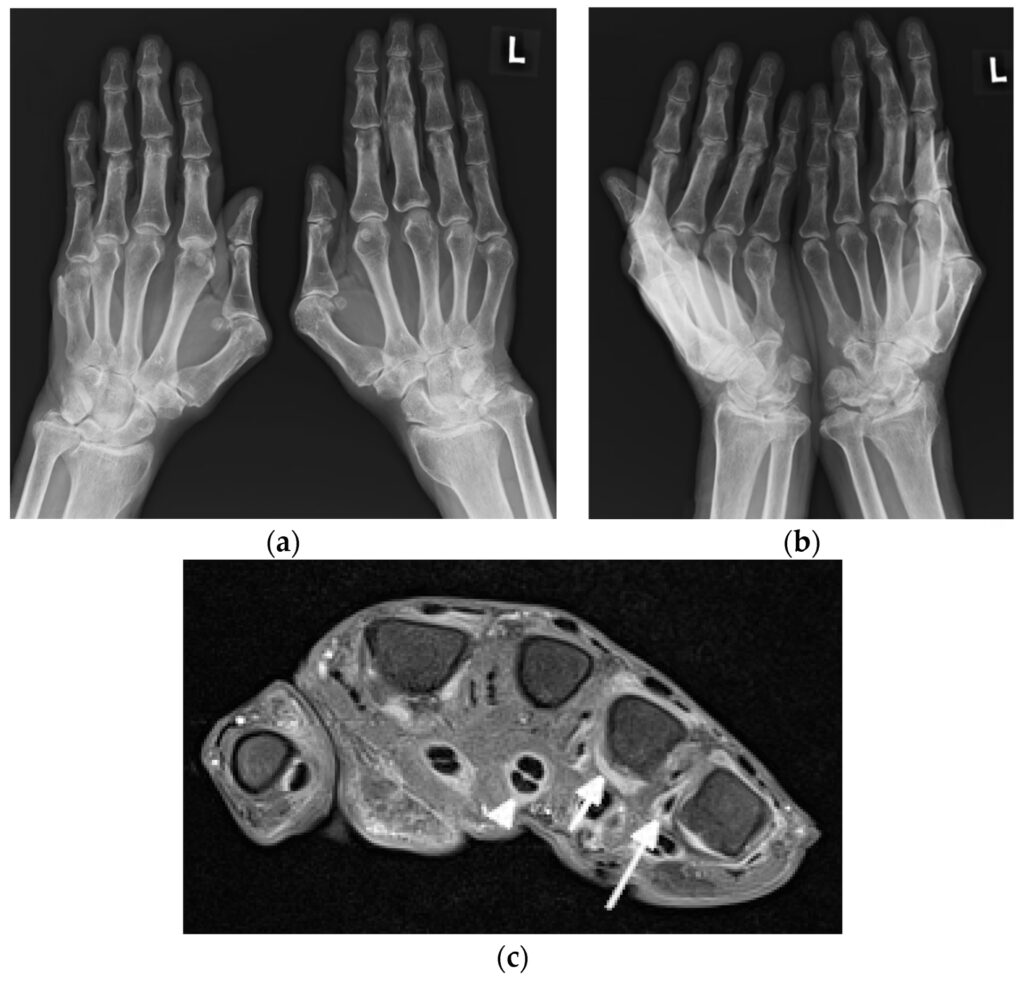

Hvad Viser Røntgenbilleder? Den Traditionelle Tilgang

Traditionelt har røntgenfotografering været det første billeddiagnostiske skridt i udredningen af ledsmerter hos lupuspatienter. Selvom røntgenbilleder kan være helt normale i de tidlige stadier af sygdommen, kan de over tid afsløre en række karakteristiske forandringer.

En undersøgelse af røntgenbilleder af hænderne hos 59 SLE-patienter viste, at mere end halvdelen (34 patienter) havde synlige abnormiteter. De mest almindelige fund var:

- Periartikulær bløddelshævelse: Hævelse i vævet omkring leddene.

- Demineralisering: En reduktion i knogletætheden omkring leddene, også kendt som periartikulær osteopeni.

Andre, mindre hyppige, men signifikante fund inkluderede:

- Fejlstillinger: Subluksation (delvis forskydning) af led, som ses ved Jaccouds artropati.

- Akral sklerose: En fortykkelse af knoglen i de yderste fingerled.

- Avaskulær nekrose: Knogledød forårsaget af nedsat blodforsyning, hvilket kan være en komplikation til både sygdommen og behandlingen med steroider.

- Bløddelsforkalkning: Aflejringer af kalcium i bløddelene omkring leddene.

- Terminal tuft resorption: En nedbrydning af knoglen i fingerspidserne.

Det er interessant, at studier har vist, at sværhedsgraden af disse radiografiske fund ikke nødvendigvis korrelerer med markører for sygdomsaktivitet i blodet, såsom lave komplementniveauer. Dette understreger, at ledsygdom ved lupus kan have sin egen dynamik, uafhængigt af den systemiske inflammation.

Avanceret Billeddannelse: Et Dybdegående Kig med Ultralyd og MR-scanning

Mens røntgen er god til at vise knoglestrukturer, har den begrænsninger, især i de tidlige faser og i vurderingen af bløddele som ledhinder, sener og ledbånd. Her har ultralyd og MR-scanning revolutioneret diagnostikken af lupusgigt.

MR-scanning: Det Ultimative Værktøj til Detaljer

MR-scanning (Magnetisk Resonans) giver den mest detaljerede visualisering af alle strukturer i et led – knogler, brusk, ledhinder, sener og ledbånd. Dens største fordel i forbindelse med lupusgigt er evnen til at påvise knoglemarvsødem (Bone Marrow Edema - BME). Knoglemarvsødem er en væskeansamling inde i knoglen, som er et stærkt tegn på aktiv inflammation og ofte en forløber for udviklingen af knogleerosioner. MR-scanning er også overlegen til at kortlægge det fulde omfang af synovitis og tenosynovitis og kan opdage erosioner, som selv ultralyd kan overse. Studier har fundet knoglemarvsødem i håndleddet hos 13% til 35% af SLE-patienter.